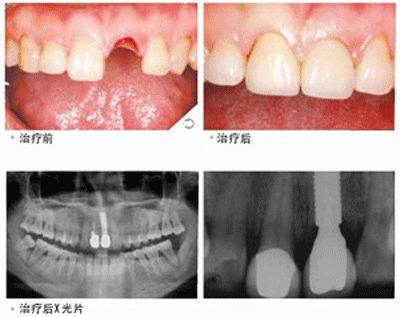

种植门牙案例分享:家住江北区的张先生因为不小心导致门牙摔掉了一颗,门牙缺失后的张先生马上打车来到了贝臣齿科。到院后种植牙医师为其做了口腔健康检查,并根据张先生的个人情况为其推荐了欧洲顶级种植体。经过一个小时的手术后,张先生的门牙又从新长了出来。